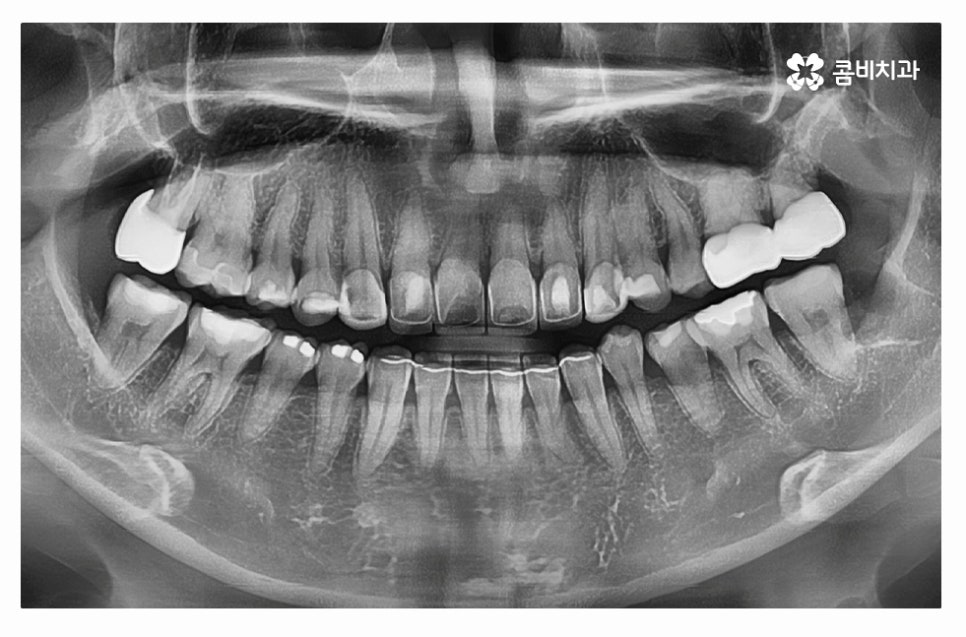

누운사랑니발치 사례를 보면서 설명을 듣는다면 더욱 이해가

잘 되실 텐데 위 사진처럼 사랑니가 어금니 방향으로

자라고 있는 경우에는 치아 사이 충치를 유발하거나

잇몸질환의 원인이 될 수도 있는데요.

이처럼 사랑니가 치아 본래의 기능을 하지 못하고 관리가

어려운 경우에는 사랑니의 뿌리가 깊어지기 전에 발치를 해야 할 수 있어요.